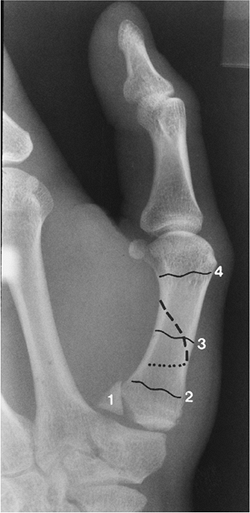

|

FIGURE 9-22

Radiograph of the thumb demonstrating an intra-articular fracture (1), Bennett fracture with lines demonstrating metaphyseal (2), diaphyseal (3), and distal neck fractures (4). |